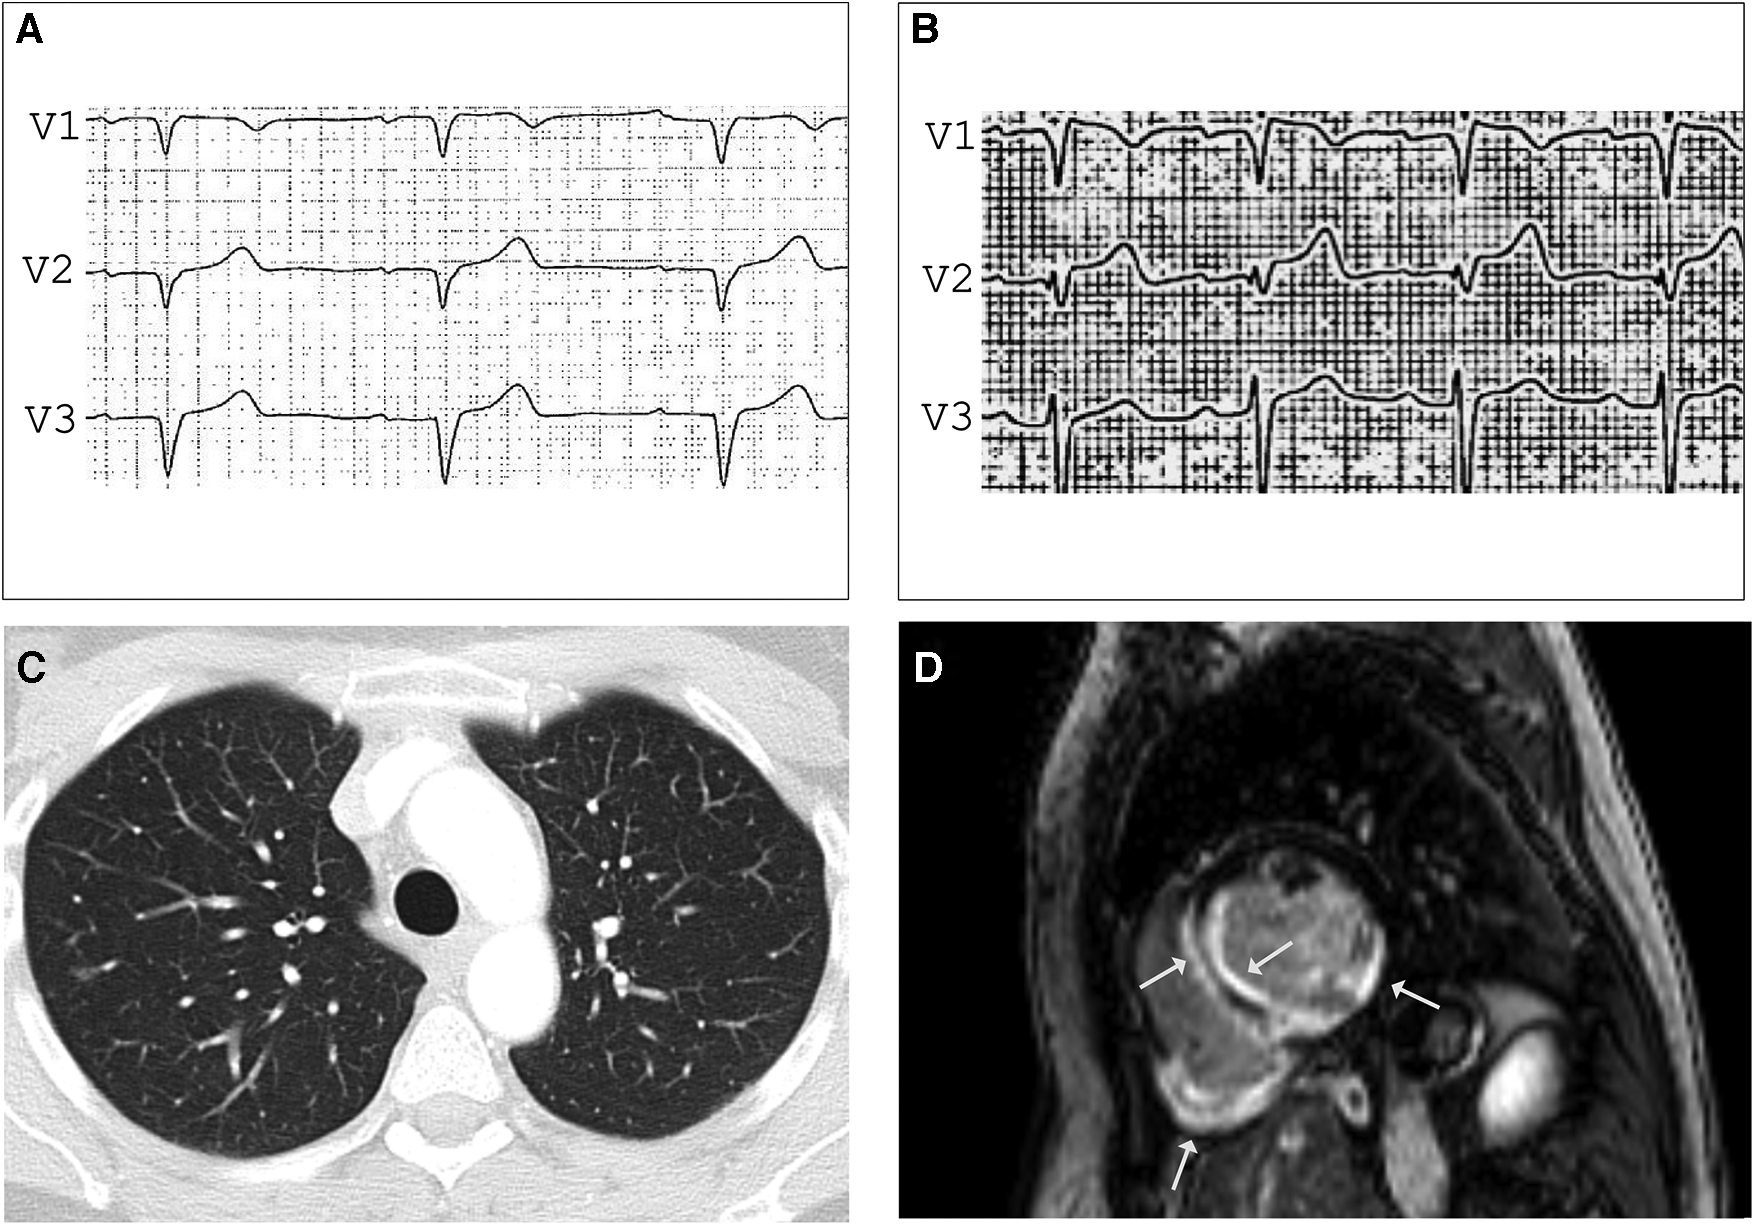

Figure 1

LGE CMR frames in short-axis (A) and 4-chamber (B)-views demonstrating striated midwall fibrosis of the septal LV wall (arrows). Ejection fraction was mildly impaired (LVEF 47%). (C) Axial-view of 18FDG-PET follow-up revealing tracer uptake in the LV Septum (arrows). (D) 18FDG-PET follow-up under immunosuppressive therapy with glucocorticoids (GC) showing no more tracer uptake indicating no cardiac inflammation under GC.

A 47-year-old female medical assistant was referred to our department due to recurrent palpitations, two prior unexplained presyncope, and suspicion of ventricular septal defect. There was no family history of sudden cardiac death (SCD), cardiomyopathy, or sarcoidosis. The echocardiography showed basal thinning of the interventricular septum but no septal defect. The ECG showed left anterior fascicular block, frequent PVCs, and normal QTc. The Ajmaline provocation test unmasked a coved-type ST segment elevation in V1 with inverted T-waves (Figures 2A,B), suggesting the Brugada syndrome. To exclude the presence of structural heart disease, a CMR was performed 2 days after the Ajmaline provocation test was conducted, revealing an impaired LVEF of 41% with normal-sized heart chambers. Surprisingly, the T2 mapping demonstrated edema at the posterior wall of the right ventricle, as well as at the septal, anterior, and posterior walls of the left ventricle (LV). Furthermore, late gadolinium enhancement (LGE) was observed in the subendocardial to intramyocardial regions of the basal septal and inferolateral LV wall, as well as the entire posterior wall of the right ventricle (Figure 2D). A contrast-enhanced CT showed small, irregular parenchymal foci dispersed in both lungs without evidence of mediastinal lymphadenopathy or fibrosis (Figure 2C). Due to the signs of inflammation shown in the CMR and CT scans, suggesting stage 3 pulmonary sarcoidosis, we performed an EMB, which was positive for epithelioid granuloma with multinucleated cells, confirming the diagnosis of CS. Considering the impaired LVEF, the presence of LGE, and two previous episodes of presyncope, an electrophysiological study for risk stratification was performed that resulted in the induction of polymorphic VT, and a dual chamber implantable cardioverter-defibrillator (ICD) was implanted. During the 6-month follow-up, the device interrogation revealed episodes of polymorphic non-sustained VT and spontaneously terminating ventricular fibrillation (VF).

Figure 2

ECG before (A) and after (B) Ajmalin provocation test unmasking coved-type ST segment elevation in V1 suggesting BrS. (C) Contrast-enhanced CT showing small, irregular foci in both lungs compatible with pulmonary sarcoidosis stage 3. LGE CMR frame in short-axis - view (D) revealing subendocardial to intramyocardial LGE in the basal septal and inferolateral LV wall and the entire right ventricular posterior wall (arrows), LVEF was mildly impaired (41%) with normal-sized heart chambers.